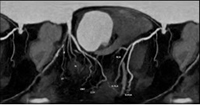

冠脉CTA检查是排查心脏隐患、防范猝死风险的重要手段,也是我们了解自身心脏状况的便捷选择。

检查后,很快就能出具影像诊断结果,清晰呈现心脏血管真实状况,能让隐患无所遁形。

通过冠脉CTA,能清晰地看出多种心脏相关疾病: